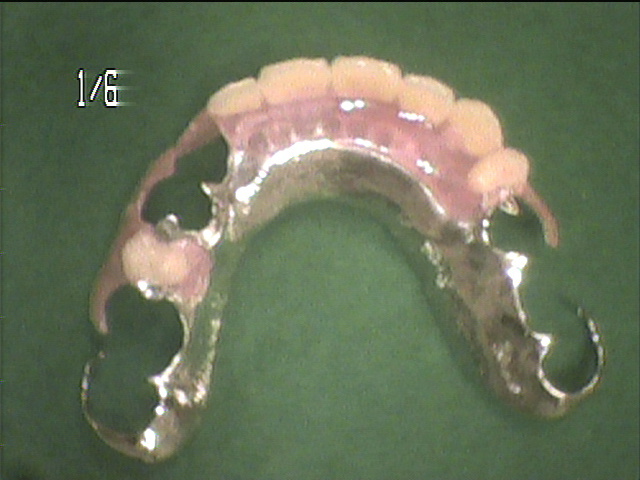

治療中写真

- 保存できない歯は抜歯し、奥歯の治療を行ったのち、「目立たない入れ歯」を作成しました。

- 内側は金属の薄いプレートを使い、舌感を良くし、唇側は金具を使わないタイプの審美性に優れた義歯を作成しました。